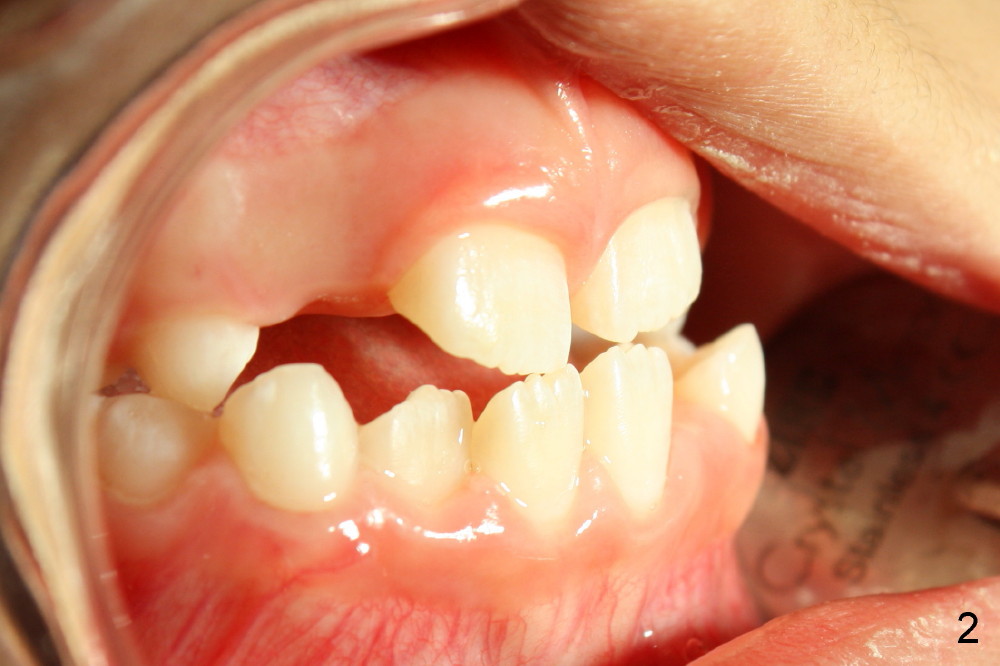

A 8-year-old girl presents malocclusion (Fig.1-3). What is the initial treatment?

Jenny: The girl has cross bite of both the anterior and posterior teeth. I think that first we need to expand her palate.